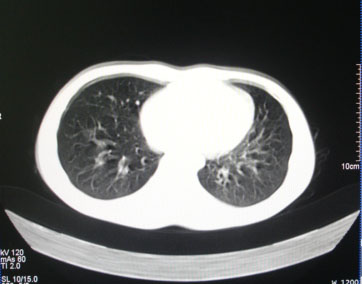

标题: CT26938:单发肺窗

病人17岁。咳嗽伴血丝痰2年?外院x片示左上肺椭圆形影,疑胸腺瘤

左肺尖见占位,建议上传纵隔窗及向上扫描。

左上纵隔占位性病变?